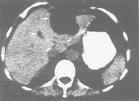

7.CT检查有助于诊断和鉴别诊断。